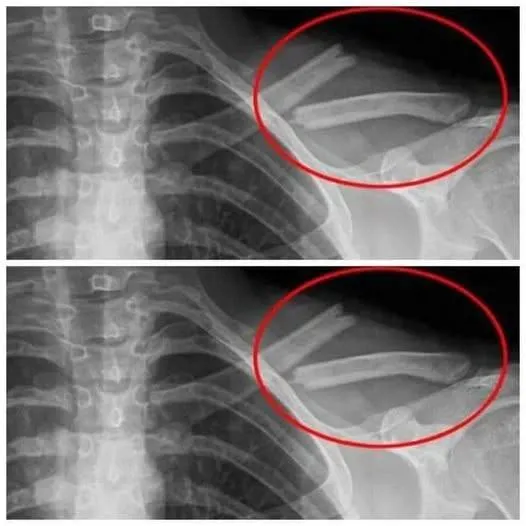

1. SOFT DRINKS + SOFT BONES + OSTEOPOROSIS

If you don’t want to have to depend on calcium supplements all your life, regulate your soda intake immediately. It greatly weakens the basic skeleton that our form depends on, leading to a lot of joint pain and other detrimental health damages.